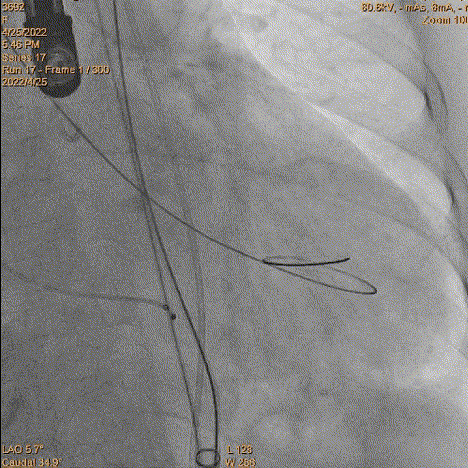

3、球囊预扩:由于钙化严重球囊无法通过,遂使用圈套器抓捕球囊。

套圈器抓球囊过瓣

20mm球囊预扩

导丝位置改变

对侧上圈套器准备

4、跨瓣:瓣膜跨瓣出现困难,计划使用圈套器。由于没有22F大鞘,内连鞘无法拆卸,选择左侧穿刺导入导管。右侧双导丝,送入Lunderquist,心室较大。扩张后,血压较稳定。经尝试无法退球囊,撤出系统。通过对侧使用抓捕器,将导丝全撤,导入AL1.0导管重新跨瓣。鉴于左侧入路有角度,使用泥鳅导丝带上导管,做圈套器。顺利抓住J型导丝,抓捕器顺利抓捕瓣膜过瓣。